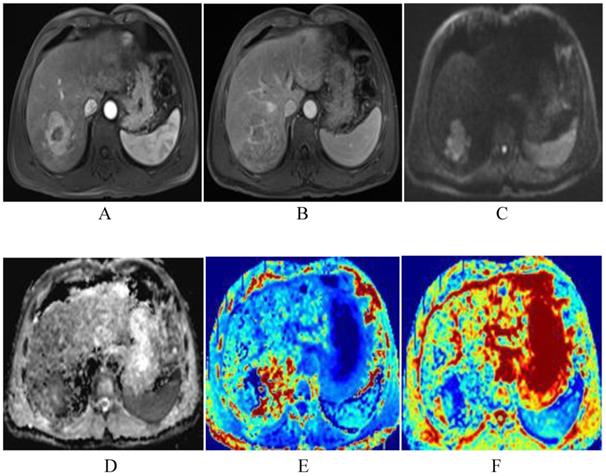

Figure 8

The same patient with Fig. 2 after TACE. The degree of lesion enhancement is significantly reduced and DWI signal is decreased (A-C). ADC and MD map after TACE show higher signal intensity than the residual tumor. The values for the lesion are 1.55×10-3mm2/s and 2.15×10-3mm2/s respectively (D-E). Fig. F is the kurtosis map, showing lower signal intensity than the residual tumor. The value for the lesion is 0.45.

J Cancer Image